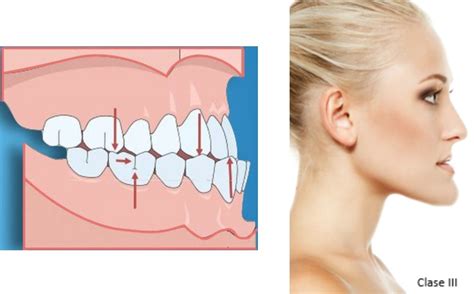

La maloclusión de clase III, también conocida como prognatismo mandibular, es una de las alteraciones dentofaciales más complejas. Implica una relación incorrecta entre la mandíbula y el maxilar superior, con un adelantamiento de la primera respecto al segundo. En este artículo exploraremos cuál es el origen de esta maloclusión, sus tipos, los tratamientos para corregirla y las consecuencias funcionales y estéticas de no tratarla.

La clase III es una anomalía que afecta a los huesos maxilares y/o a los dientes. Se produce cuando hay una desalineación entre la arcada superior y la inferior, ya que la mandíbula está más adelantada que el maxilar superior. Esta malformación se describe por la presencia de una discrepancia anteroposterior entre la mandíbula y el maxilar superior, esto es, ambas estructuras óseas se encuentran desalineadas entre sí.

Esta maloclusión no solo afecta a la estética facial, sino también a la masticación y el habla y, en algunos casos, a la respiración. Por eso, es conveniente tratarla cuanto antes.

En este caso, el trastorno también afecta a los huesos maxilares. Se debe a un sobrecrecimiento de la mandíbula o a una falta de desarrollo del maxilar superior. Es el tipo más complejo y puede requerir una combinación de ortodoncia (para corregir la posición de los dientes) y cirugía ortognática (para corregir la posición y el tamaño óseo). En los casos de prognatismo mandibular, la mandíbula está desarrollada por exceso en relación con el maxilar y el arco dentario inferior se extiende hacia adelante más allá del superior, causando una maloclusión de Clase III, también conocida como underbite.